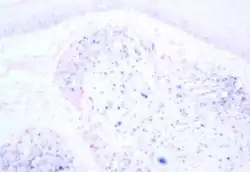

| Microscope image of tumour showing HPV positivity by in situ hybridization | |

There is no standard HPV testing method in head and neck cancers,[63] both in situ hybridization (ISH) and polymerase chain reaction (PCR) are commonly used.[44][64] Both methods have comparable performance for HPV detection; however, it is important to use appropriate sensitivity controls.[65] Immunohistochemistry (IHC) staining of the tissue for p16 is frequently used as a cost-effective surrogate for HPV in OPC, compared to ISH or PCR.[66][67][68] There is a small incidence of HPV-negative p16-positive disease, accounting for about 5% of HPV-OPC.[66]